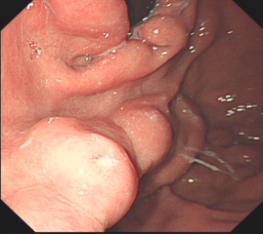

内镜下食管异物取出